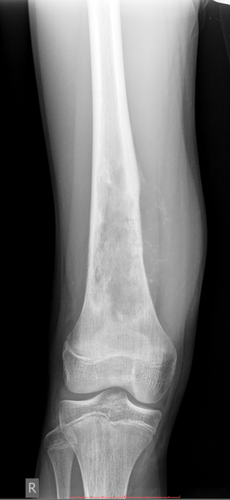

Рентген диагностика заболеваний опорно-двигательного аппарата

Рентгенография костей